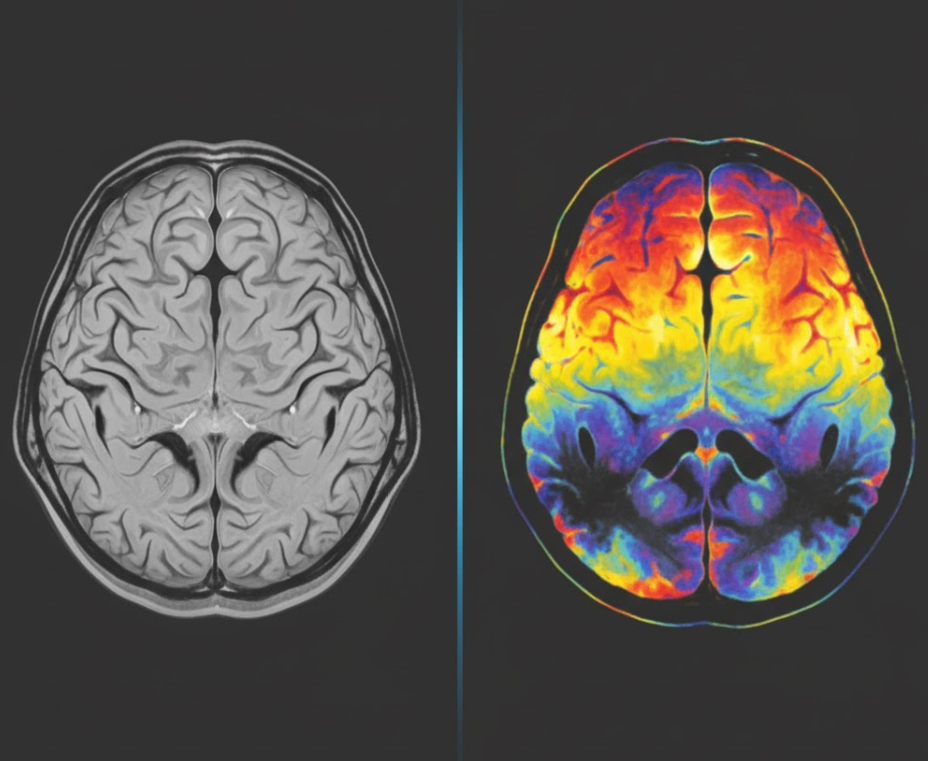

뇌 MRI(자기 공명영상)와 PET(양전자방출단층촬영)의 가장 큰 차이점은 '무엇을 보느냐'에 있습니다. MRI는 뇌의 '구조적'인 모습을, PET는 뇌의 '기능적'인 상태를 보여줍니다. 뇌 MRI는 강력한 자기장과 고주파를 이용해 우리 몸속 수소 원자의 신호를 받아 컴퓨터로 재구성하여 뇌의 해부학적 구조를 사진처럼 선명하게 보여주는 검사입니다. 방사선 노출이 없다는 장점이 있으며, 뇌의 특정 부위가 위축되었는지(줄어들었는지), 뇌경색이나 뇌출혈의 흔적이 있는지, 혹은 뇌종양이나 뇌수두증처럼 인지 저하를 유발할 수 있는 다른 구조적 문제가 있는지를 확인하는 데 매우 유용합니다. 알츠하이머 치매의 경우 기억을 담당하는 '해마' 부위의 위축 소견을 확인하는 데 결정적인 역할을 합니다. 반면, 뇌 PET는 포도당이나 특정 단백질에 방사성 동위원소를 붙인 의약품을 체내에 주입한 후, 이 물질이 뇌 안에서 어떻게 분포하고 대사 되는지를 촬영하는 검사입니다. 뇌세포는 활동할 때 포도당을 에너지원으로 사용하므로, 포도당 대사가 활발한 곳은 밝게, 기능이 저하된 곳은 어둡게 나타납니다. 이를 통해 뇌의 어느 부분의 기능이 떨어져 있는지를 시각적으로 확인할 수 있습니다. 특히 알츠하이머병 환자에게 특징적으로 나타나는 후두정엽 부위의 대사 저하를 발견하거나, '아밀로이드 PET' 검사를 통해 원인 물질인 베타 아밀로이드 단백질의 침착 여부를 직접 확인할 수도 있습니다. 정리하자면, MRI가 뇌의 '설계도'를 보는 것이라면, PET는 그 설계도 위에서 '전기가 어떻게 사용되고 있는지'를 확인하는 검사라고 할 수 있습니다.